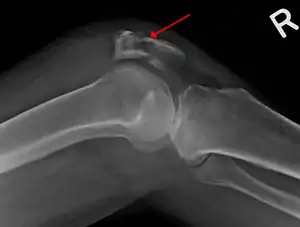

The patella can break in various ways depending on the way it is injured, and into two or more pieces.[1] Types include transverse, with one fracture line and is the most common type,[5] marginal, osteochondral and the rare vertical type, or stellate, where a direct compression force gives rise to a comminuted pattern.[5][7] Patella fractures can be further classified as displaced, where the broken ends of bone do not line up correctly and separate by more than 2mm, or undisplaced and stable where pieces of bone remain in contact with each other.[1][7] If fragments of patella bone stick out from the skin it is known as an open patella fracture, and closed if the overlying skin is intact.[1]

Osteochondral fracture of patella

Vertical patella fracture